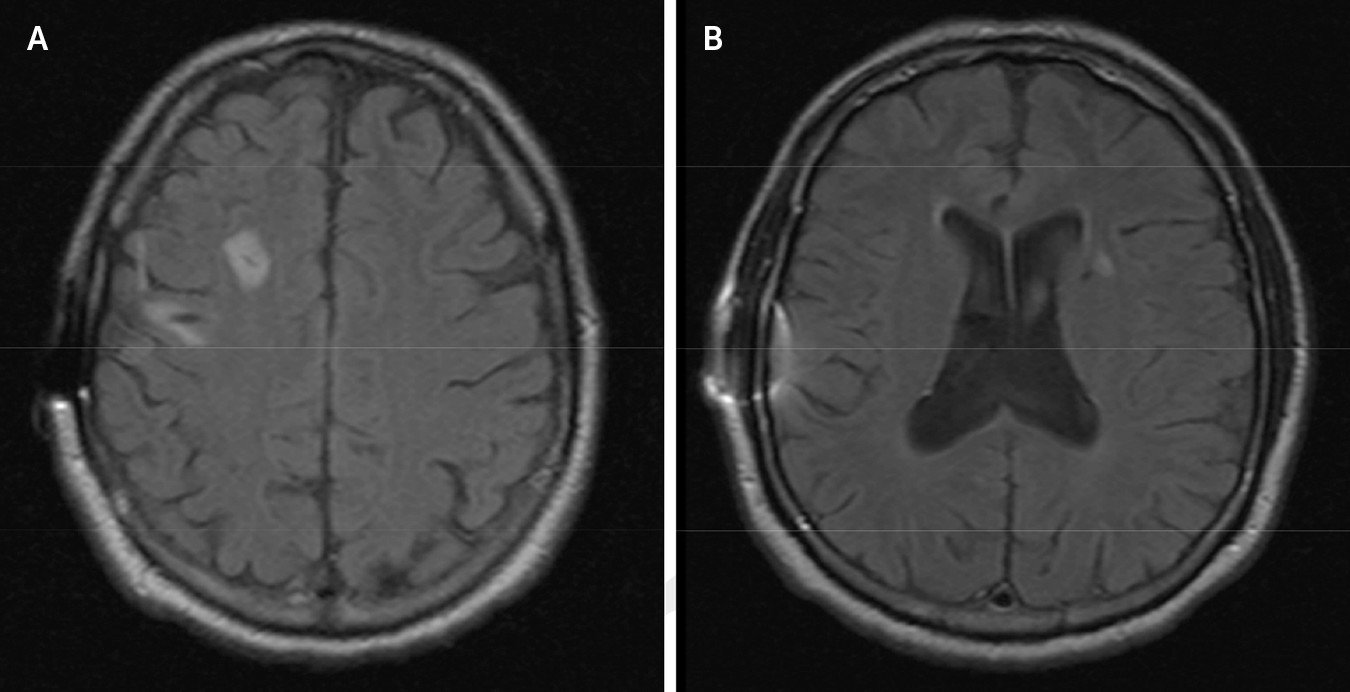

患者脑部 MRI 扫描

2016 年的一项研究描述了一名 69 岁的男子,他中风后产生了对幽默的强迫性需求。

这位病人特别喜欢分享令人捧腹大笑的笑话,经常半夜把妻子叫醒,就为了给她讲一个趣事。所以她好心地请他把笑话写下来,以免吵醒她。

第一次与神经科医生团队见面时,这名男子带来了“大约 50 页纸,里面全是他的笑话,其中大部分是双关语或带有性或排泄内容的愚蠢笑话”。

这名男子被诊断患有 “幽默癖”(Witzelsucht) ,这是一种以持续不断的幽默欲望为特征的症状集。通常情况下,他的笑话要么时机不当,要么内容冒犯,但讲笑话的人却浑然不觉,反而沉浸在自己的幽默之中。